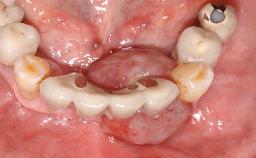

Surgical treatment of a 67-year-old male patient exhibiting an extended edentulous space in the anterior maxilla after the removal of three hopeless incisor teeth.

The case concludes with the presentation of the final prosthesis and the esthetic outcome, demonstrating stable soft tissue conditions and stable bone crest levels at the 3-year follow-up.

# of Teeth 4

# of Implants 2

Prosthesis Type FDP